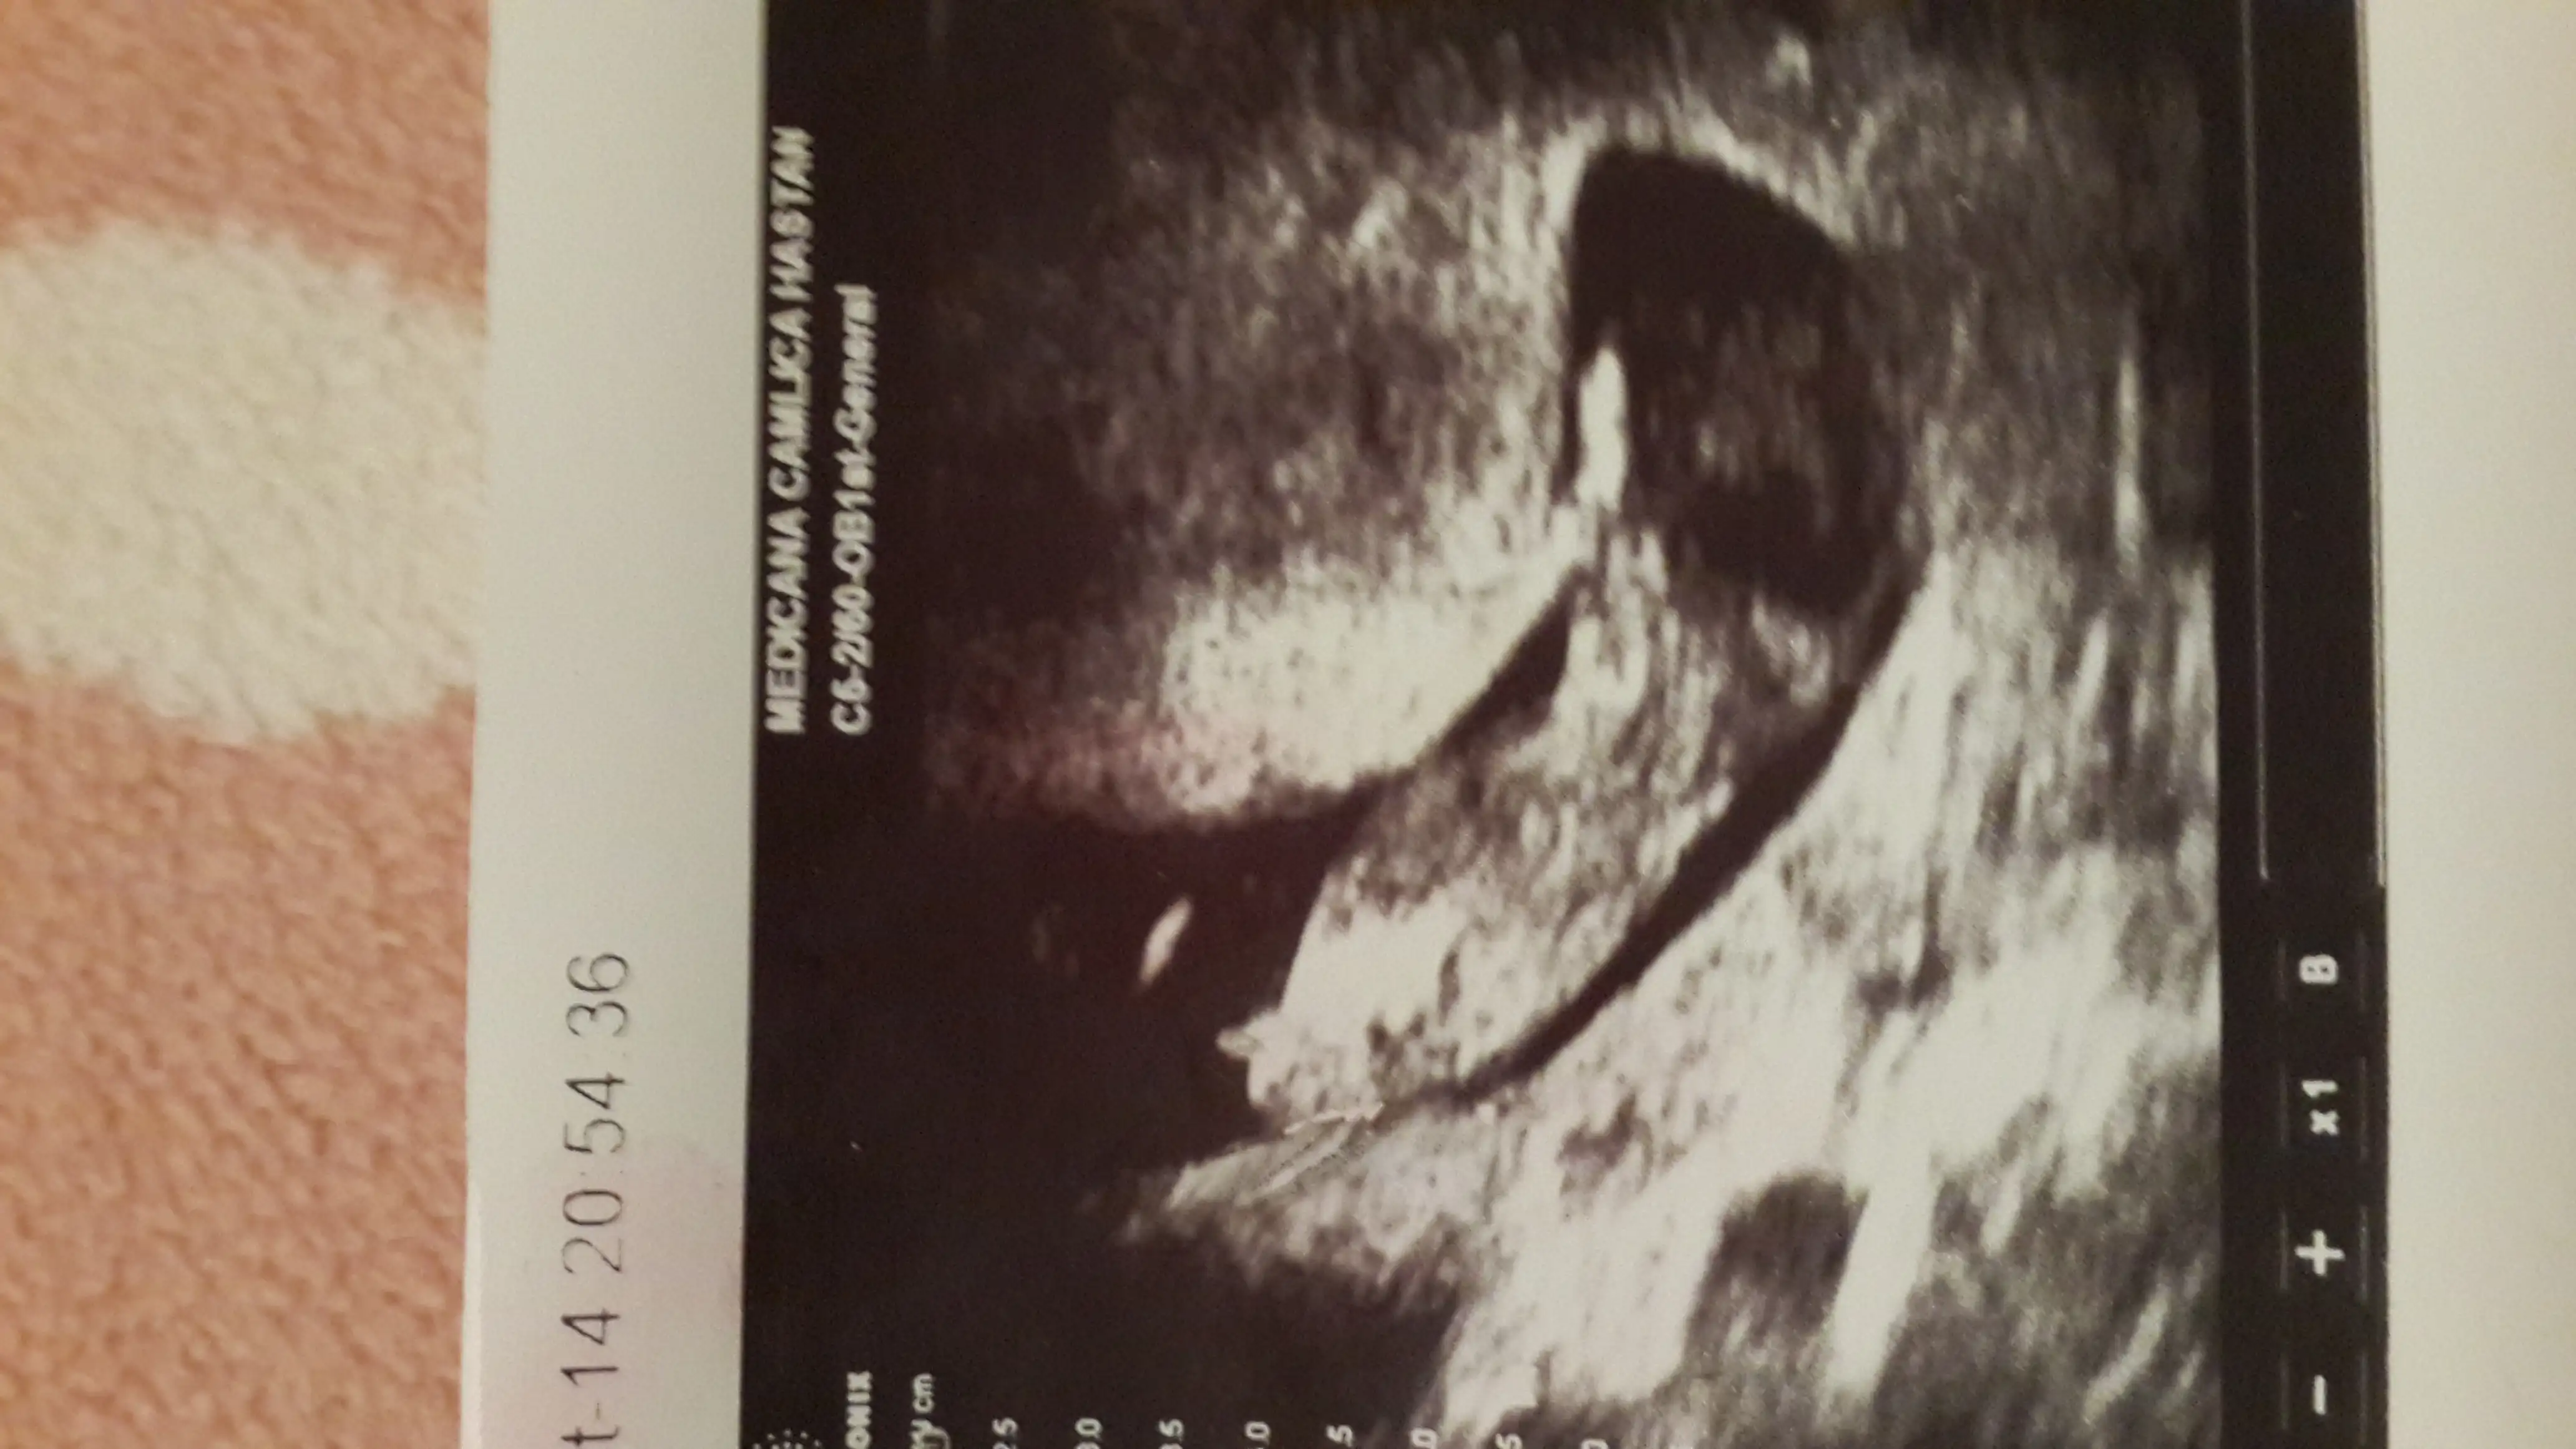

Mrb kizlar rica etsem nub teorisinden anlayanlar yardimci olabilir mi acaba? Yukledigim foto 12 hafta+2 simdiden tesekkurler..